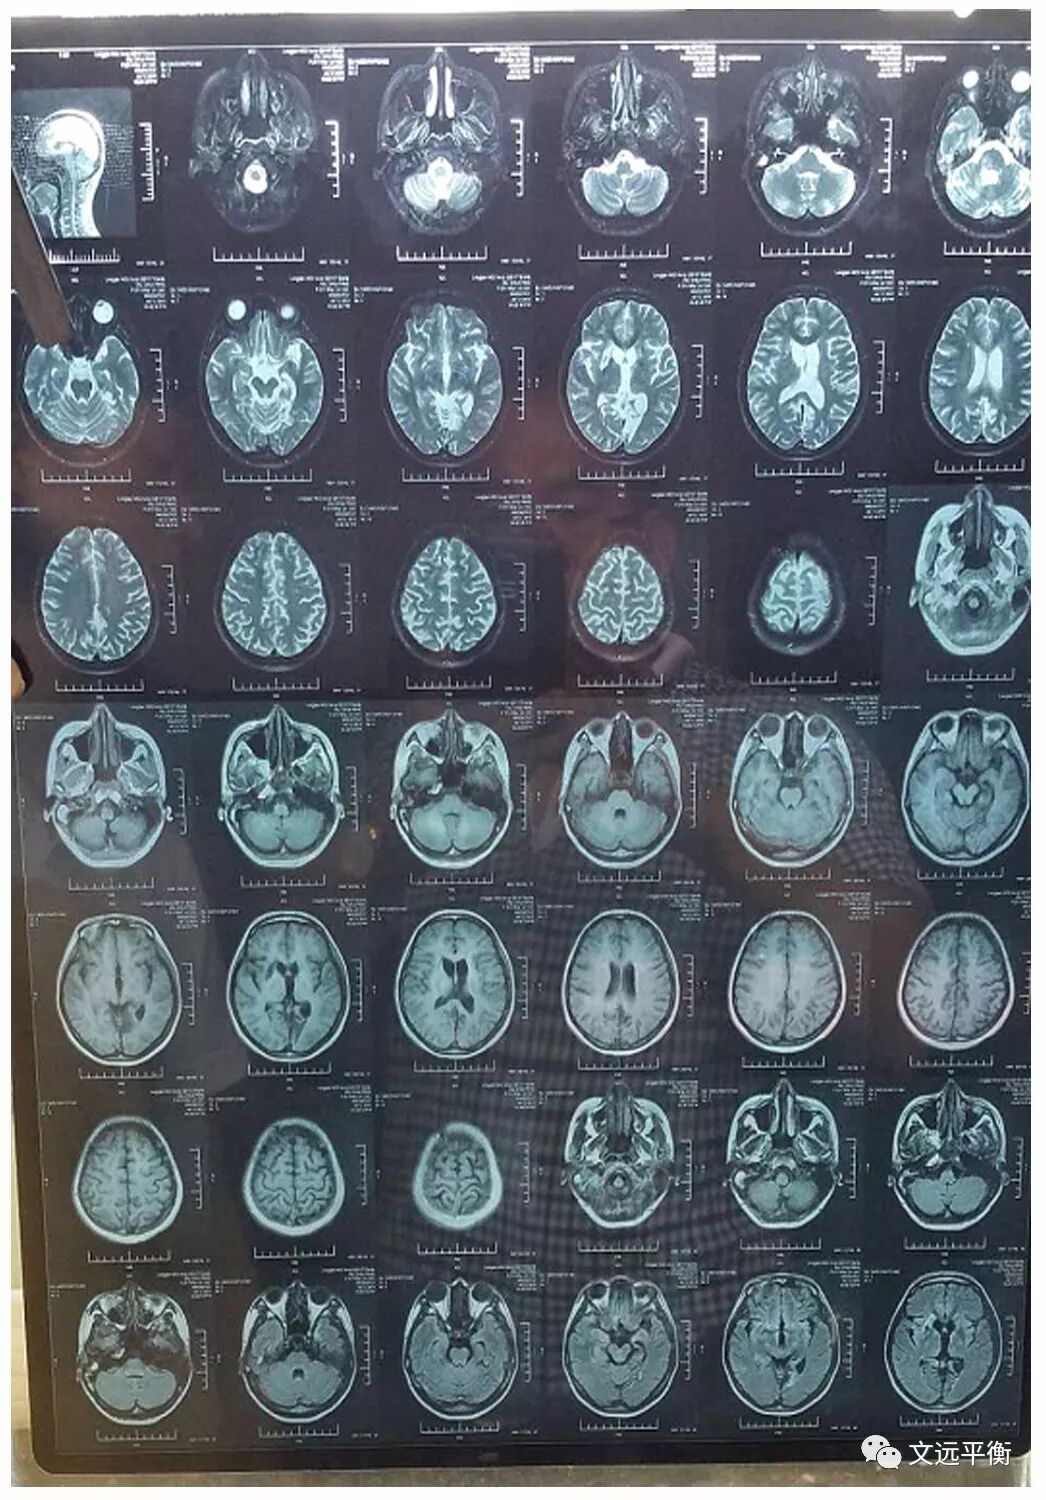

1.4影像检查:脊柱全片X片示(2016.03.24龙岩市第二医院):颈椎腰椎侧弯,腰骶角加大。三维CT示(2016.03.24龙岩市第二医院)枢椎齿状突与寰椎左右右侧块间距不等。

4.4.1第1疗程治疗后,手脚不自主运动次数及频率明显减少。记忆力有所恢复,失眠症状明显改善,由原来1天最多睡1个小时到现在每天可睡4-5个小时。复查颅脑MRI(2016.7.13龙岩市第二医院)提示:右侧基底节区,左枕叶.右侧额叶多发软化灶并周围胶纸增生,右侧额骨术后改变?

影像资料对比:图一、二。MRI平扫+增强+灌注扫描(2013.2.25宣武医院)报告提示:脑内多发异常信号,梗死伴渗血?血管炎?右侧乳突炎)

图四、五:复查颅脑MRI(2016.7.13龙岩市第二医院)提示:右侧基底节区,左枕叶.右侧额叶多发软化灶并周围胶纸增生,右侧额骨术后改变?